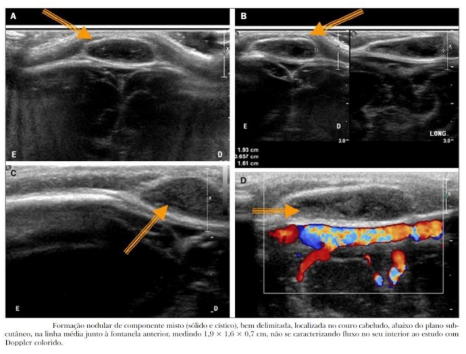

Paciente do sexo masculino, 10 meses de idade, com nódulo palpável no couro cabeludo na região mediana, junto à fontanela bregmática. Solicitada USG de couro cabeludo com o seguinte resultado:

Enunciado 1570446-1

Fonte: US nas lesões do couro cabeludo pediátrico / Diniz FV et al

Com base no resultado do exame, qual a principal hipótese diagnóstica: